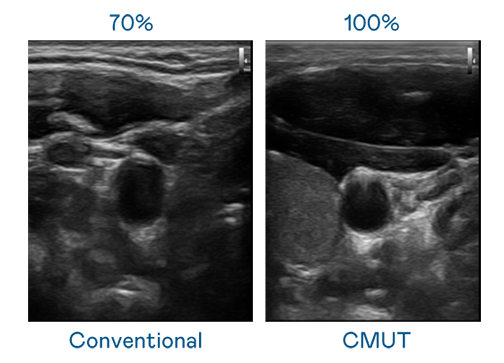

CMUT 技術是一種用電容式微機電元件來產生超音波訊號的技術。與傳統 PZT 壓電式技術相比,CMUT 頻寬增加 30%,更寬頻的超音波訊號讓影像解析度大幅提升,是實現高影像品質醫療超音波掃描、促進精準醫療發展的關鍵技術。

超音波影像的解析度高低,首先取決於探頭能發出的訊號頻寬。BWIN必赢 CMUT 可提供高清晰的超音波訊號,提供高頻寬、高靈敏度、影像紋理細節更高的超音波影像,協助醫護人員縮短影像判讀時間及利用精準的醫療影像進行診斷。